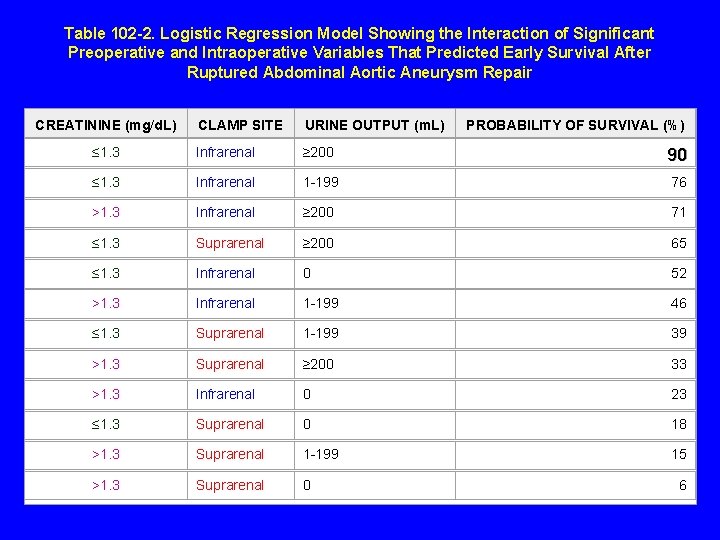

Table 102 -2. Logistic Regression Model Showing the Interaction of Significant Preoperative and Intraoperative Variables That Predicted Early Survival After Ruptured Abdominal Aortic Aneurysm Repair CREATININE (mg/d. L) CLAMP SITE URINE OUTPUT (m. L) PROBABILITY OF SURVIVAL (%) ≤ 1. 3 Infrarenal ≥ 200 90 ≤ 1. 3 Infrarenal 1 -199 76 >1. 3 Infrarenal ≥ 200 71 ≤ 1. 3 Suprarenal ≥ 200 65 ≤ 1. 3 Infrarenal 0 52 >1. 3 Infrarenal 1 -199 46 ≤ 1. 3 Suprarenal 1 -199 39 >1. 3 Suprarenal ≥ 200 33 >1. 3 Infrarenal 0 23 ≤ 1. 3 Suprarenal 0 18 >1. 3 Suprarenal 1 -199 15 >1. 3 Suprarenal 0 6